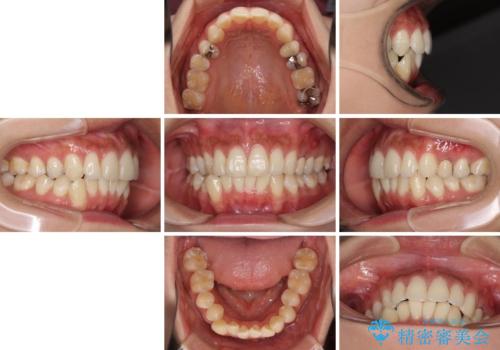

八重歯の再矯正 インビザラインでストレスなく矯正治療

- 学生の頃に矯正治療を行ったものの、保定を怠けてしまったことによる後戻りを気にして来院された患者様です。

根管治療が必要な歯があったため、矯正治療前に根管治療を行い、その後はインビザラインにより矯正治療を行うこととしました。

矯正治療後には根管治療を行った歯の補綴治療を行うこととしました。

下顎の八重歯が上顎歯列に収まる過程で咬みにくさがありましたが、最終的には、咬み合わせも安定し、きれいに歯列を整えることができました。